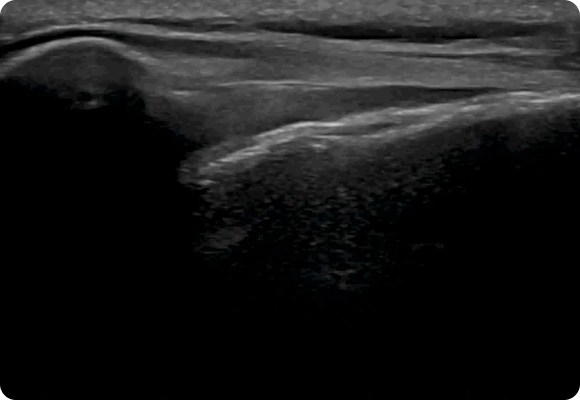

초음파 검사를 통해 어깨 관절낭과 회전근개, 점액낭, 인대 등 심부 구조물의 상태를 실시간으로 확인할 수 있습니다. 이를 바탕으로 염증 부위, 유착 범위, 근육 손상 정도를 정밀하게 파악하여 환자 개개인에 맞는 치료 방향과 재활 계획을 세울 수 있습니다.